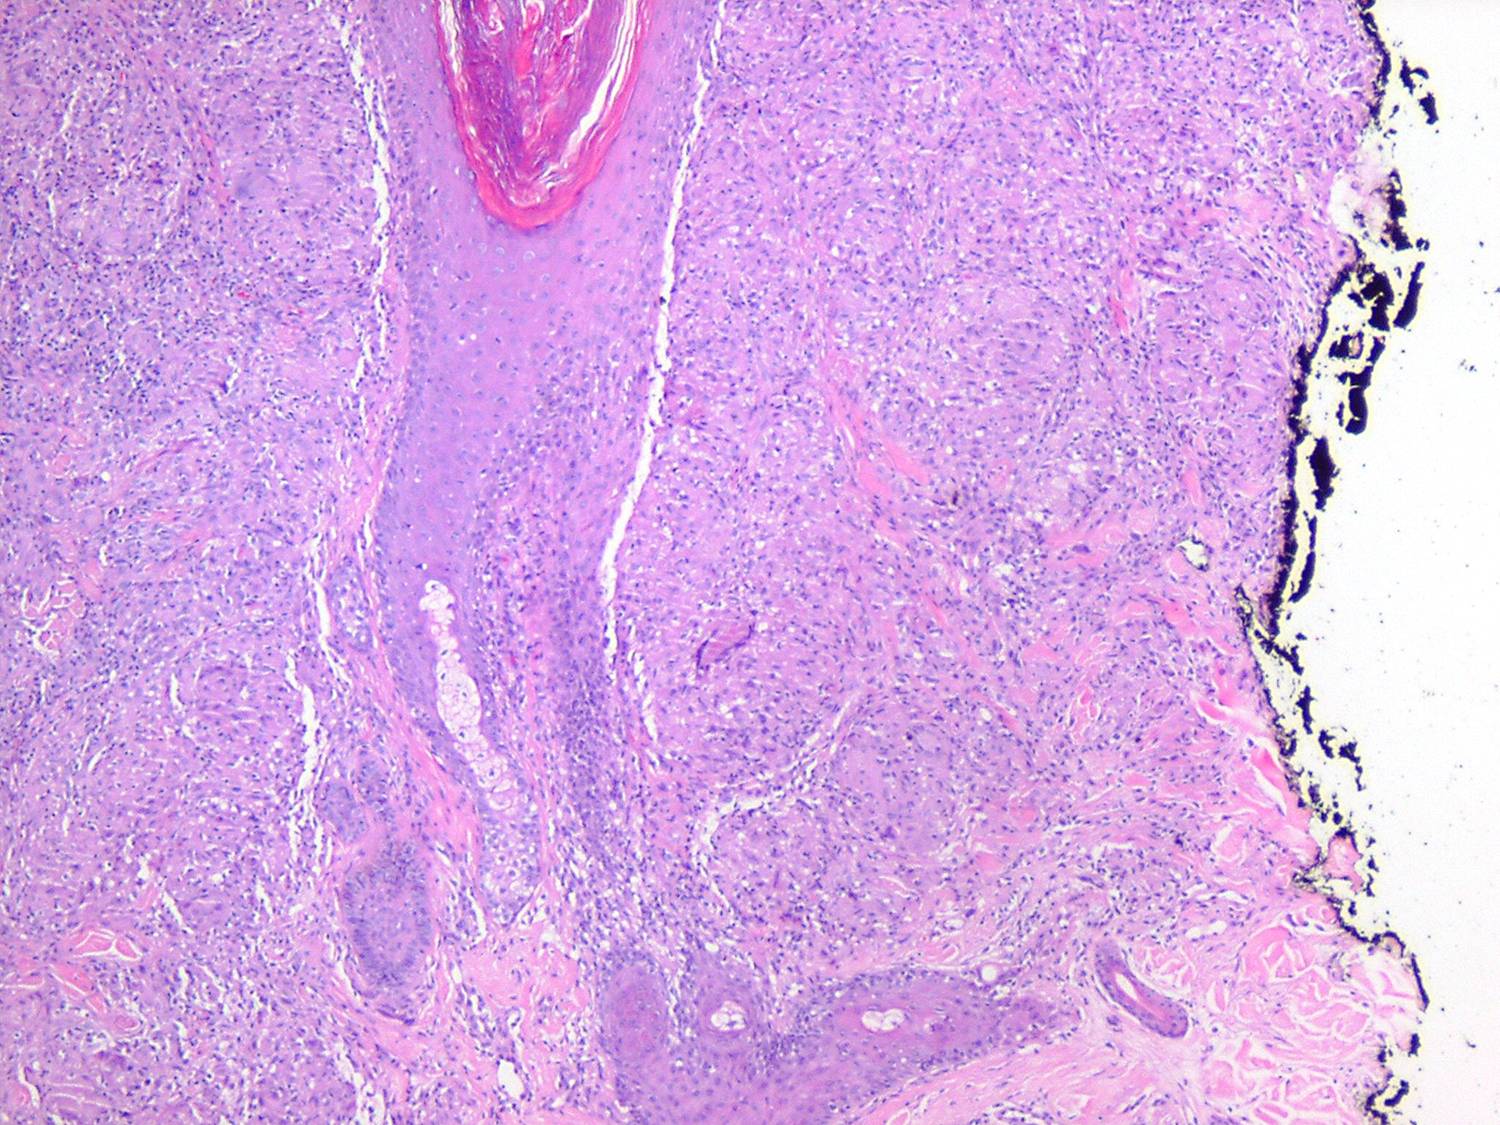

Like lesions in other organs, the cutaneous lesions of chronic, persistent sarcoidosis are characterized by the presence of circumscribed collections of epithelioid histiocytes-so-called epithelioid cell tubercles-which show little or no necrosis .

The papules, plaques, and lupus pernio-type lesions show variously sized aggregates of epithelioid cells scattered irregularly through the dermis with occasional extension into the subcutis (. In the erythrodermic form, the infiltrate shows small granulomas in the upper dermis intermingled with numerous lymphocytes

and, rarely, also giant cells . Typical sarcoidal granulomas are found in the ichthyosiform lesions , in ulcerated areas , and in atrophic lesions . Verrucous sarcoid exhibits prominent associated acanthosis and hyperkeratosis . Biopsies of

hypopigmented sarcoid may reveal granulomas, which may have a perineural component or fail to reveal granulomas . In subcutaneous nodules, larger epithelioid cell tubercles lie in the subcutaneous fat .

In typical cutaneous lesions of sarcoidosis, the well-demarcated islands of epithelioid cells contain few, if any, giant cells. Those that are present are usually of the Langhans type. A moderate number of giant cells can be found in old lesions. These giant cells may be large and irregular in shape. In a minority of cases, giant cells contain asteroid bodies or Schaumann bodies . Asteroid bodies , which are more common, are star-shaped eosinophilic structures that, when stained with phosphotungstic acid-hematoxylin, produce a center that is brown-red with radiating blue spikes . Schaumann bodies are round or oval, laminated, and calcified, especially at their periphery. They stain dark blue because of the presence of calcium. Neither of these two bodies is specific for sarcoidosis: They have been observed in a variety of other granulomas, including those of leprosy, tuberculosis, foreign-body reactions, and necrobiotic xanthogranuloma .

Classically, sarcoid has been associated with only a sparse lymphocytic infiltrate, particularly at the margins of the epithelioid cell granulomas . Because of the scarcity of lymphocytes, the granulomas have been referred to as "naked" tubercles. However, lymphocytic infiltrates in sarcoid may occasionally be dense, as in tuberculosis . Occasionally, small foci of fibrin or necrosis showing

eosinophilic staining is found in the center of some of the granulomas . A reticulum stain of sarcoid reveals a network of reticulum fibers surrounding and permeating the epithelioid cell granulomas. If the granulomas of sarcoidosis involute, fibrosis extends from the periphery toward the center, with gradual disappearance of the epithelioid cells . Fibrosis, however, is minimal to absent in most examples of sarcoidosis, with the exception of the morpheaform variant, where it is prominent {191}. Other features that may sometimes be seen include elastophagocytosis, increased dermal mucin, and lichenoid inflammation .

Tuberculoid leprosy, which may show granulomas in association with only a sparse lymphocytic infiltrate, can also be difficult to distinguish from sarcoidosis. Only 7% of cases of tuberculoid leprosy show acid-fast bacilli, and then only a few, so that they may easily be overlooked . The most likely place to find bacilli is within degenerated dermal nerves (the granulomas of tuberculoid leprosy form around dermal nerves that are undergoing necrosis). The granulomas of tuberculoid leprosy show small areas of central necrosis more often than those of sarcoidosis. In addition, the granulomas of tuberculoid leprosy, in contrast with those of sarcoidosis, follow nerves and therefore often appear elongated . Clinical correlation may be required to distinguish between these two diseases. For example, in the United States, leprosy virtually can be excluded if a patient has not been in an endemic area (either in a foreign country or where it is carried in armadillos domestically, e.g., Texas and Louisiana) or has not had prolonged close contact with another individual with the disease